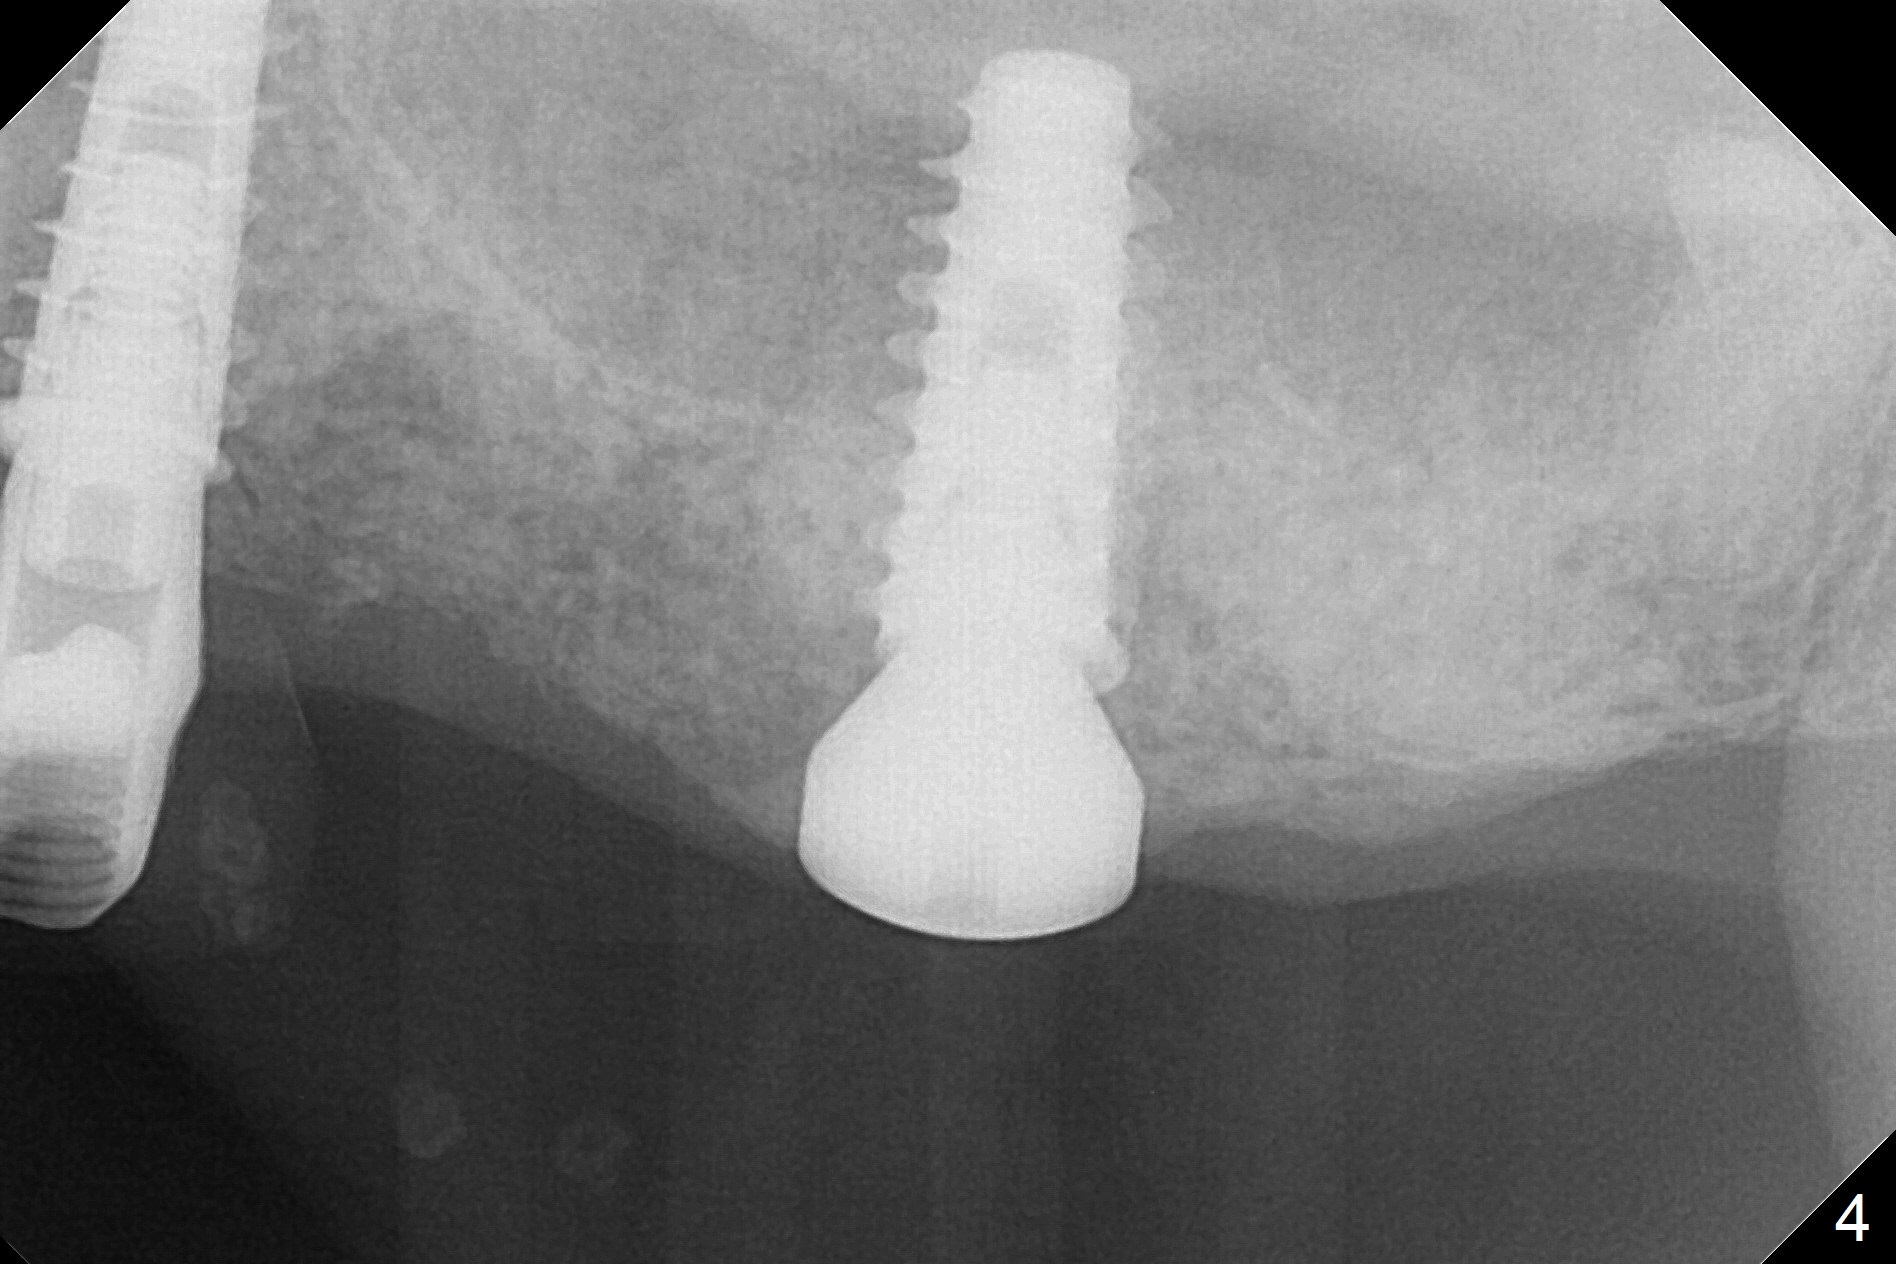

A fistula is found apical to #13 immediate implant 9 months postop (Fig.1). It is curetted without bony defect. Osteotomy at #15 is accomplished with traditional tapered osteotomes from 2 to 5 mm for 11 mm deep. Although the patient is a little uncomfortable with tapping (as compared to Magic Expanders), a 4.5x11 mm dummy implant is placed 2 mm subgingival with primary stability (Fig.2). Finally a 5x11 mm IBS implant (2 mm longer than the previous one) is placed with insertion torque > 50 Ncm; a 6x2 mm healing abutment is placed (Fig.3,4). The advantages of the flapless surgery (because of the wide ridge) include no allograft or suture. The fistula apical to #13 implant disappears 3 days postop (Fig.5), while the gingiva attaches to the healing abutment at #15 (Fig.6).